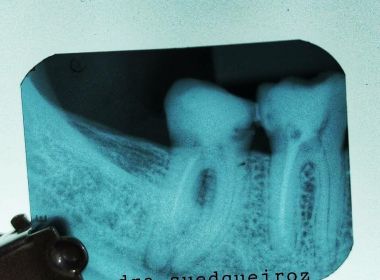

Sued Queiroz lembra de um caso recente em que uma paciente a procurou com dor afirmando que havia feito um canal com outro dentista. Ao radiografar o local, Sued constatou que o canal tinha sido feito "pela metade", e a paciente teve que se submeter a um novo procedimento e tratamento.